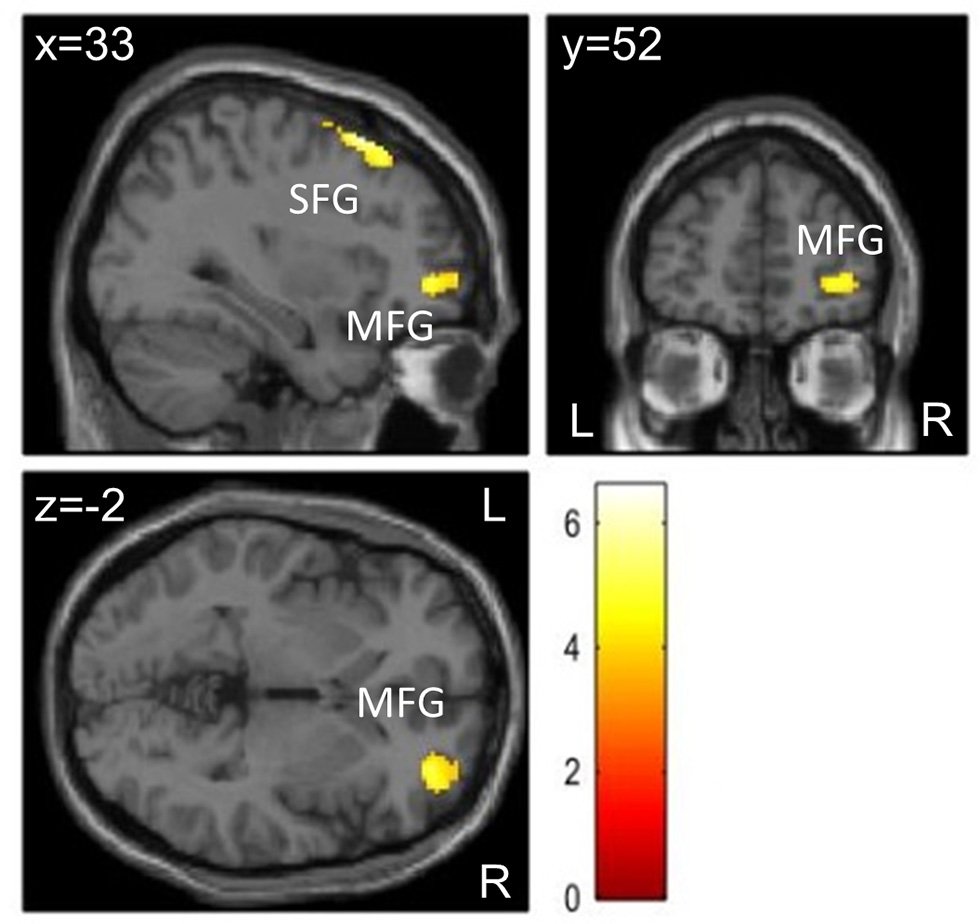

Figure 3. Clusters showing differences in brain activation during (A) congruent and (B) incongruent trials of the flanker task between the two conditions in higher fit patients (n = 12) at the level p < 0.05 (FWE-corrected on cluster level, initial voxel threshold 0.001 uncorrected). Colored areas indicate greater activation in the control condition (Movie) than in the exercise condition. (A) In congruent trials, activation differences were found in two clusters with peak activation in the right precentral gyrus (PreCG) and right middle temporal gyrus (MTG). (B) In incongruent trials, activation differences were found in three clusters with peak activation in the medial part of the superior frontal gyrus (SFGmed), right middle frontal gyrus (MFG), and the paracentral lobule (PCL).

During incongruent trials, patients showed decreased activation in the exercise compared to the control condition in three clusters: the first cluster extended from the medial to the left lateral part of the superior frontal gyrus, the right midcingulate cortex, and right dorsolateral prefrontal areas; the second cluster extended from the right middle frontal gyrus to right precentral and superior frontal regions (lateral part of premotor cortex); the third cluster was located in the paracentral lobule including the supplementary motor area (medial part of premotor cortex) (Figure 3B).

Figure 4. Brain activation differences during visual stimulation at T1 for Movie – Exercise in patients with ADHD (n = 20) at the level p < 0.05 (FWE-corrected on cluster level, initial voxel threshold 0.001 uncorrected). Activation differences were found in two clusters with peak activation in the right superior frontal gyrus (SFG) and right middle frontal gyrus (MFG).